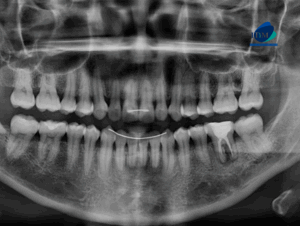

Paciente femenino de 27 años acude a IDM- Sede Jesús María con motivo de consulta para control de ortodoncia y a la evaluación de la